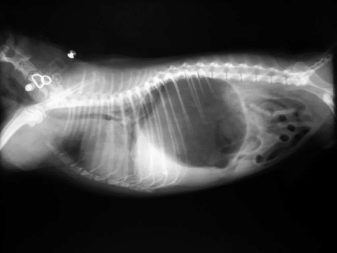

The owner should be aware of the regular preventive treatment of fleas, ticks and, if necessary, visit the vet. With proper maintenance and proper care, the Hungarian Sheepdogs can live from 10 to 12 years. The animal has strong immunity, so it does not often get sick. However, among the Comonorians there is a predisposition to such illnesses:

3. Bloating and torsion of the stomach. The reasons that cause this ailment include one-time daily feeding of the animal in a large volume, as well as the activity of the pet immediately after eating.

Inversion of the stomach